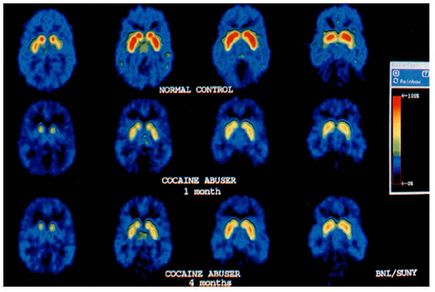

One of his most important studies looked at cocaine abusers among a population of veterans. The findings – illustrated here and “reproduced thousands and thousands of times” – suggest permanent changes in the brains of cocaine addicts. Even four months after stopping cocaine use, dopamine receptors had not recovered as the researchers had predicted. Dr. Hitzemann’s own brain was scanned and included as the normal control in this image.During the lecture, Dr. Hitzemann also spoke about colleagues who influenced the direction of his research. He met John Crabbe, PhD, now Director, Portland Alcohol Research Center, at a conference in Puerto Vallarta, Mexico, in 1986. Dr. Crabbe was the person who got him interested in mouse genetic research and how genes play into drug abuse.

Figure 1

Volkow, N. D., Fowler, J. S., Wang, G.-J., Hitzemann, R., Logan, J., Schlyer, D. J., Dewey, S. L. and Wolf, A. P. (1993), Decreased dopamine D2 receptor availability is associated with reduced frontal metabolism in cocaine abusers. Synapse, 14: 169–177. doi: 10.1002/syn.890140210